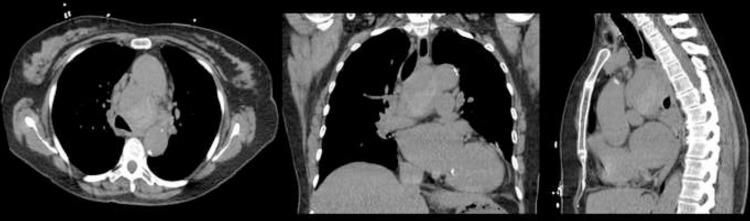

Bronchial artery aneurysm and pseudoaneurysm is a rare but life-threatening diagnosis due to catastrophic complications from rupture. Prompt detection and management is key to prevent complications. CT angiogram and digital subtraction angiography are preferred diagnostic imaging modalities. Being very uncommon, these entities can be misdiagnosed as a nonspecific mediastinal soft tissue mass, which can lead to delay in diagnosis and inappropriate or delayed management. We present a case of 72-year-old woman with incidentally detected large bronchial artery pseudoaneurysm, incorrectly classified as mediastinal malignancy at outside facility, receiving follow-up exams for 2 years, before correct diagnosis and management.

支气管动脉动脉瘤和假性动脉瘤是一种罕见但危及生命的诊断,因为破裂会引发灾难性并发症。及时检测和处理是预防并发症的关键。CT血管造影和数字减影血管造影是首选的诊断成像方式。由于非常罕见,这些病变可能被误诊为非特异性纵隔软组织肿块,从而导致诊断延迟以及治疗不当或延误。我们报告一例72岁女性病例,其偶然发现巨大支气管动脉假性动脉瘤,在外院被错误分类为纵隔恶性肿瘤,接受了2年的随访检查,最终才得以正确诊断和处理。